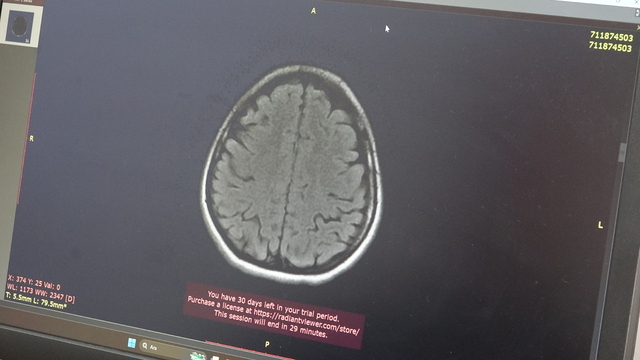

Tıp alanında yapay zeka, makine öğrenimi ve dijital teknolojilerin gelişimine büyük önem verdiklerini belirten Prof. Dr. Murat Terzi, "Son yıllarda bu alandaki çalışmalar hızla artarken, biz de OMÜ'de özellikle nörobilim ve nöroloji alanında yapay zeka uygulamaları üzerinde yoğunlaşıyoruz. Amacımız, hastalıkların erken tanısını koymak ve hastalığın seyrini bireyselleştirerek, kişiye özel tanı ve tedavi yöntemleri geliştirmek. Bu doğrultuda hastaların beyin MR’ları ve omurilik MR’larının görüntü analizlerini yapıyoruz. Görüntüleme yöntemleri sayesinde beyin damar tıkanıklığı mı, multiple skleroz (MS) gibi hastalıklar mı olduğu gibi teşhisleri daha hızlı ve doğru koymayı hedefliyoruz" diye konuştu.

Hastalara uygulanan tedavi süreci hakkında bilgi veren Prof. Dr. Terzi, "Çalışmalarımız sadece görüntüleme analizleriyle sınırlı kalmıyor. Hastaların yürüme hareketlerini detaylı şekilde inceleyerek, hangi sinir sistemlerinin etkilendiğini belirlemeye çalışıyoruz. Bu sayede hastalığın etkilediği alanları daha iyi tespit edebiliyoruz. Ayrıca hastalığın tanısı ve takibi için sadece görüntüye değil, kan ve bel suyu örnekleri gibi biyolojik verilere de önem veriyoruz. Bunun yanında hastaların konuşma ve ses kayıtlarını analiz ederek nörolojik durumları hakkında ek veriler elde ediyoruz. Tüm bu farklı veri kaynaklarını bir araya getirerek kapsamlı bir değerlendirme yapıyor, hastaya özel hassas tıp ve bireyselleştirilmiş tedavi stratejileri geliştirmeyi hedefliyoruz" dedi.

Yapay zeka ile nöroloji bilimini entegre ederek, hastalık teşhisinde hızlanmayı hedeflediklerini söyleyen Terzi, "Bu çalışmalar multidisipliner bir yaklaşım gerektiriyor. Nöroloji alanındaki uzmanlarımızın yanı sıra nörobilim bölümlerinde eğitim gören lisansüstü öğrencilerimiz, mühendislik fakültesinden destek veren mühendis arkadaşlarımızla birlikte yakın iş birliği içinde çalışıyoruz. Ekip olarak amaçladığımız, gelişmekte olan yapay zekayı doğru ve güvenilir bilgilerle eğitmek, bu teknolojinin nörolojik hastalıkların tanısında doktorlara etkin şekilde destek vermesini sağlamaktır. Yapay zeka, MR veya kan testleri gibi tanı araçlarımızın yanında doktorların karar verme sürecini destekleyerek, erken ve doğru tanı konmasına olanak tanıyor. Böylece her hastanın tedavi sürecini kendi özel durumuna göre planlayabiliyoruz. Bu sayede daha etkili, hedefe yönelik ve kişiye özel sağlık hizmetleri sunabiliyoruz" diye konuştu.